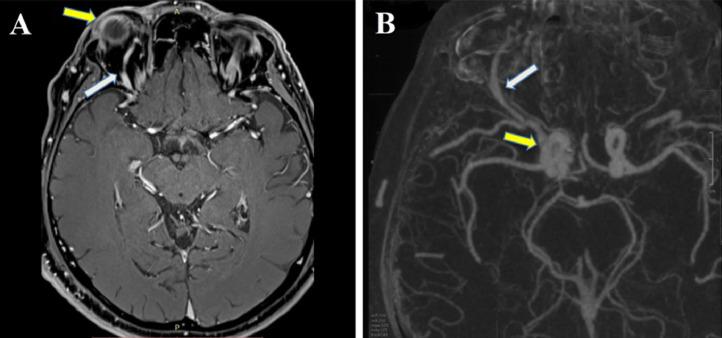

颈动脉海绵窦瘘(CCF)是一种血管畸形,其特征是一个或多个动脉流入源与海绵窦(CS)之间存在异常分流。它们可分为直接瘘和间接瘘。后者称为硬脑膜CCF,涉及颈内动脉或颈外动脉分支之间的硬脑膜瘘管连接。当传统路径不可行时,静脉的手术暴露是进入瘘管的唯一途径。我们介绍了一例通过混合方法成功治疗右侧硬脑膜CCF的患者病例。此外,通过文献综述,我们分析了这种方法可能带来的风险和益处。

https://cdn.ncbi.nlm.nih.gov/pmc/blobs/9917/9283805/7edef802fb58/gr1.jpg